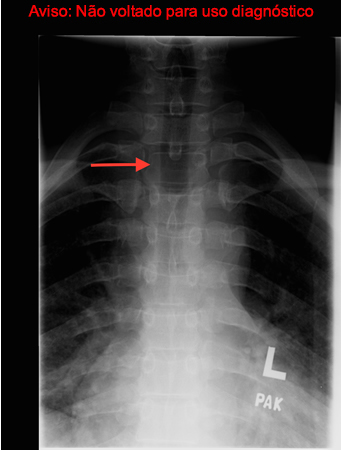

Sinal de "coruja piscando" (seta): aparência assimétrica da coluna cervical na radiografia simples causada pela destruição do pedículo

Criado por BMJ Publishing Group